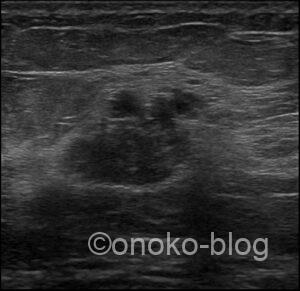

こちらの受診者様は3年前も当院でエコーを受けていただいていたので 画像を確認します。

エコー機が違うので、見え方が少し異なっているのか?

でも内部エコーが変化しているような…

このぼやっとして見える感じ…

小葉癌?DCIS?